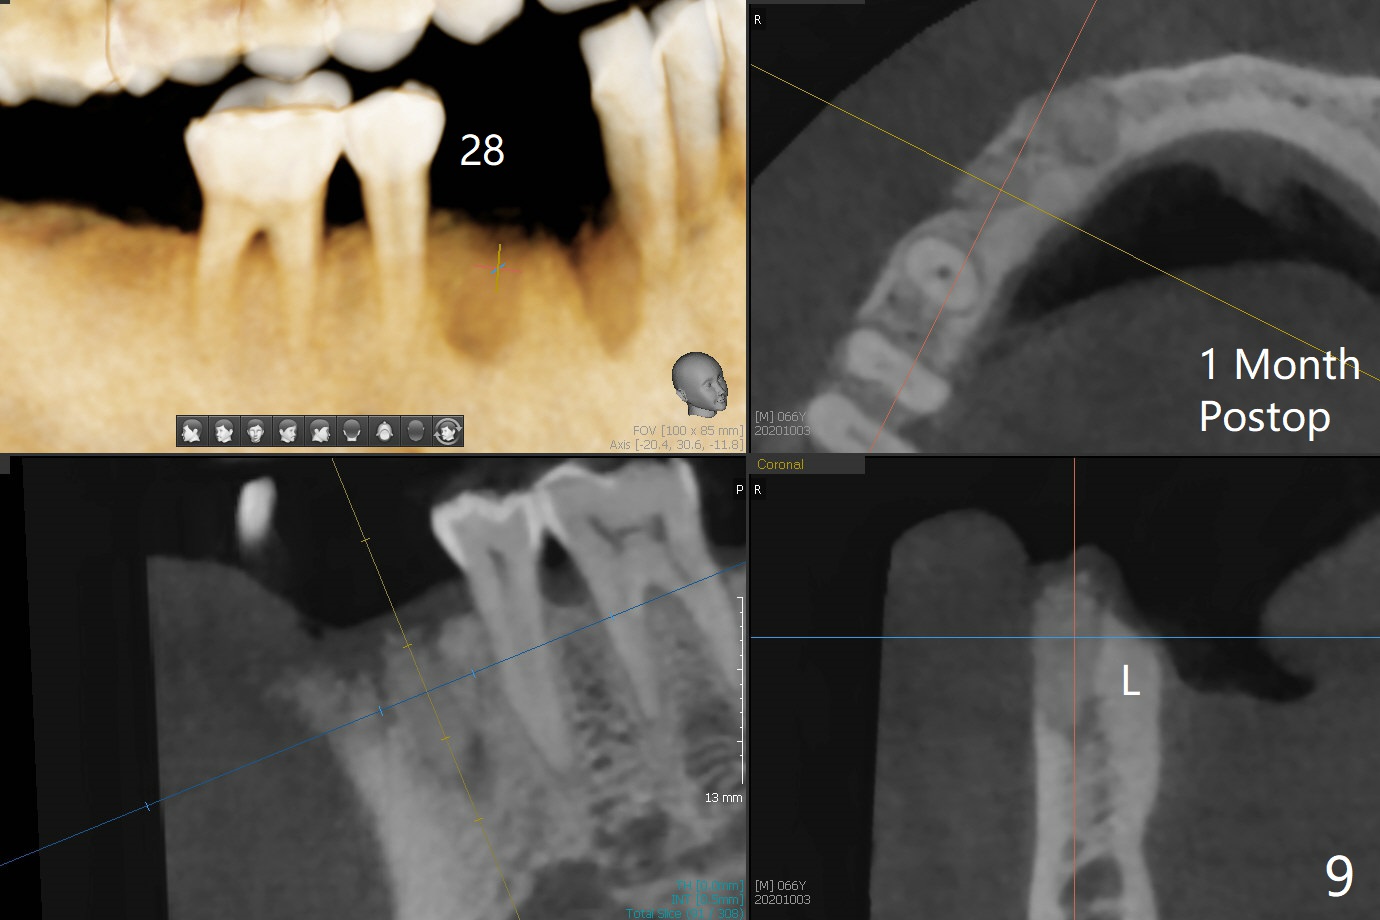

66岁男1.5年前来诊所拍摄全景片(图一),似乎27,28号牙还能保留,今天突然回来,主诉27、28区疼痛瘘道,商量决定先拔除27,28,32及右下深洗。拔除32号牙时发现它接近31区(将要植牙),必须植骨(近中部分(远中塞入胶原塞)),27,28颊侧骨板缺失(大量肉芽组织),植骨理所应当,而且必须拼命推压,但愿推到颊侧骨板,细的皮质骨没有压制感,非要加入粗的松质骨皮质骨,一张12x12毫米胎盘膜剪成两片覆盖27/28和32拔牙窝,4-0 PGA缝线固定,拍摄术后半侧全景片后(图二 (*:骨粉)),使用牙周敷料保护伤口。术后一个月27,28号牙位骨粉保持原位,而且颊侧骨板好像已经重建(图八,十一,九),似乎能植入两个植体(图十,十二)。